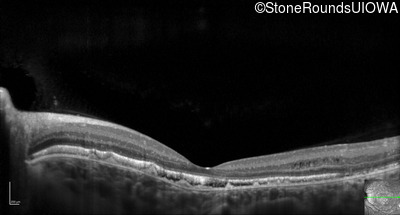

Optical Coherence Tomography - Left - 20/25 -3 sc

Exemplar / OCT Stack

OCT Stack